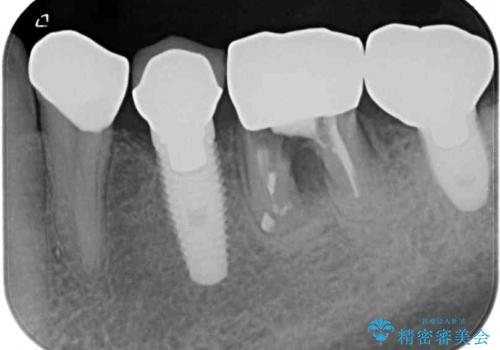

- 奥歯が割れてしまい、抜歯が必要となった患者様です。

以前にも歯が割れてインプラント治療を行いましたが、抜歯してからインプラント埋入→仮歯装着までに半年以上を要し、その間に残された歯への負担が大きくなり、セラミッククラウンが破折したことがありました。

そのため、当院に新しく導入した手法により、抜歯をした日にインプラントを埋入し、そのままを仮歯を装着することで、他の歯への負担を軽減する計画を立てました。

インプラント埋入時に植立具合の安定性を測定したところ、十分な数値が得られたため、速やかに仮歯を装着して咬合回復をさせることができました。